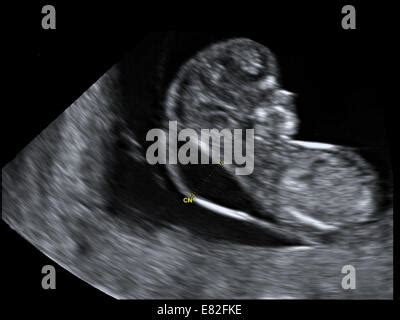

Ultraschalluntersuchung zur Nackentransparenzmessung

Zwischen der 11. und 13. Schwangerschaftswoche kann Ihr Arzt oder Ihre Hebamme eine Ultraschalluntersuchung anbieten, um die Nackentransparenz (NT) des Fötus zu messen. Dies ist der Bereich zwischen der Haut am Nacken des Fötus und der darunterliegenden Wirbelsäule. Eine verdickte Nackentransparenz kann ein Hinweis auf Chromosomenanomalien oder Herzfehler sein. Einige Krankenhäuser bieten diese Ultraschalluntersuchung an, sie wird aber hauptsächlich in Privatkliniken durchgeführt.